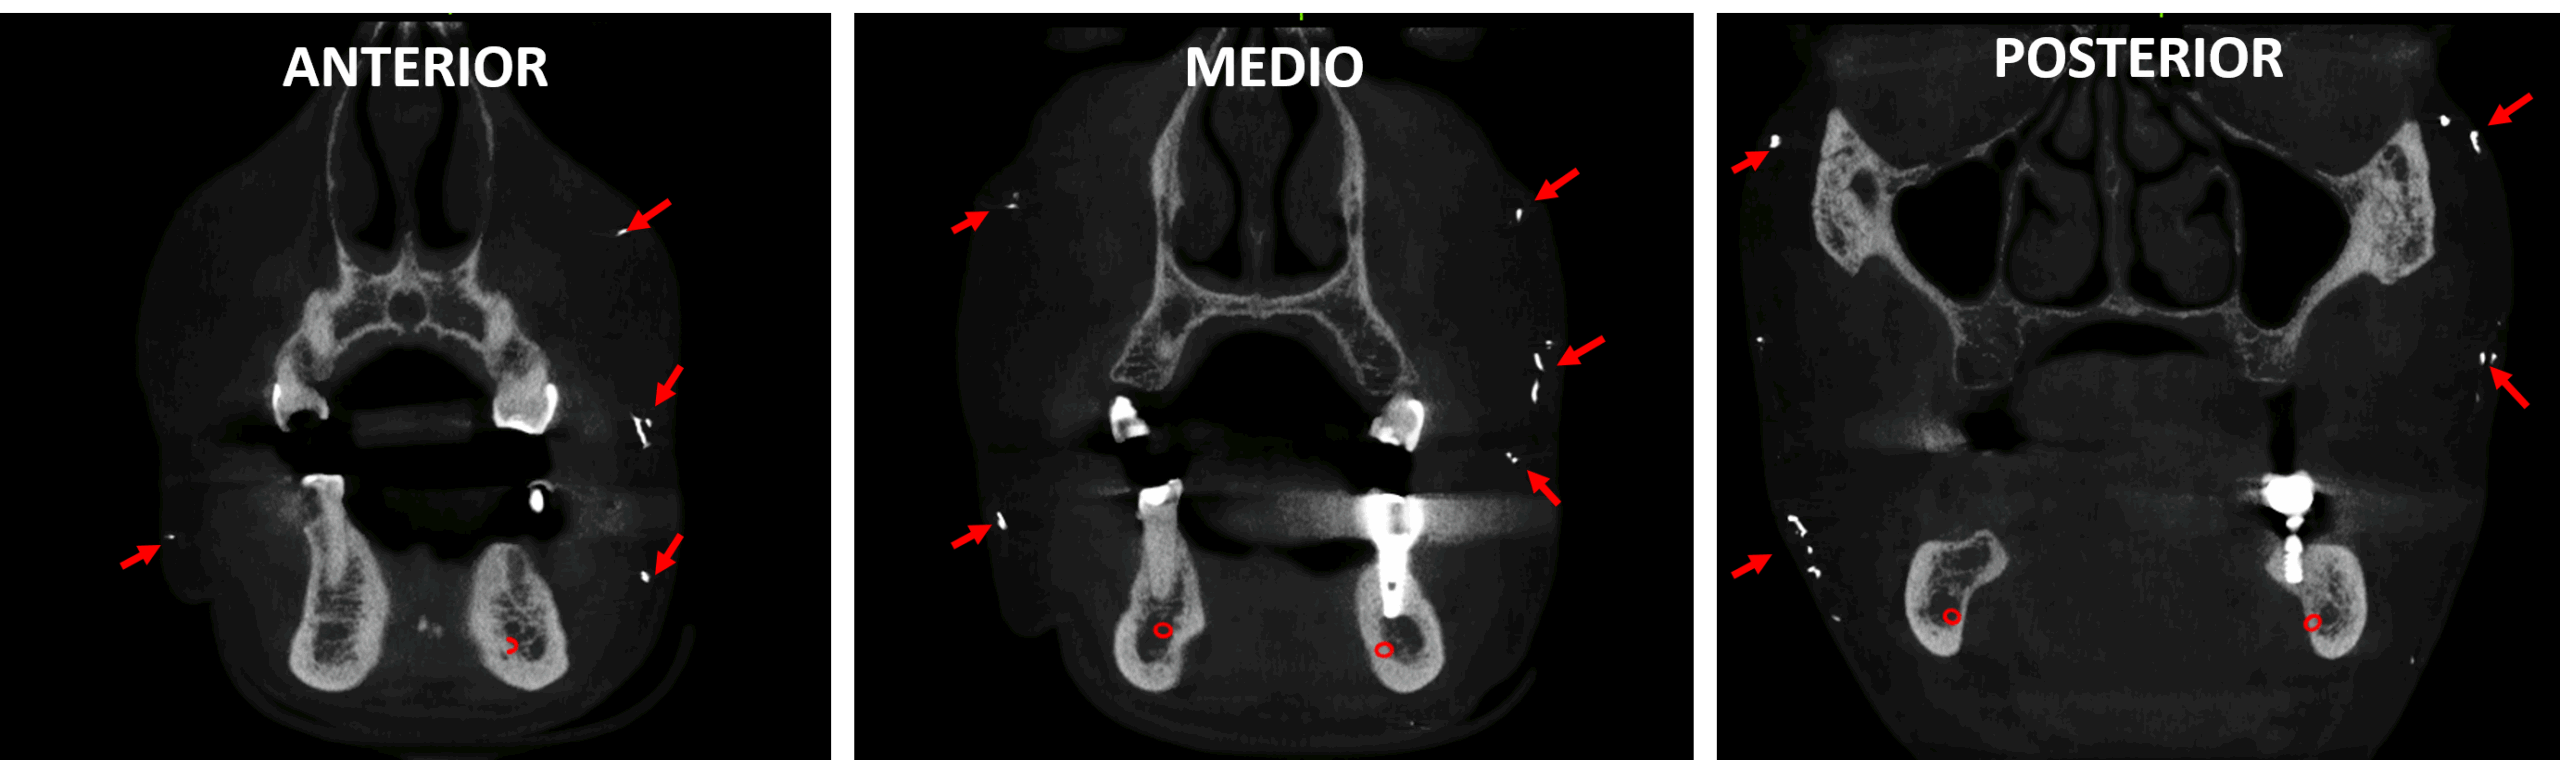

Fig.3

En cortes axiales (Fig.2) y en cortes coronales (Fig.3) se observan múltiples imágenes hiperdensas en la región submandibular, y en la región geniana en ambos lados del tejido blando facial (fechas rojas).